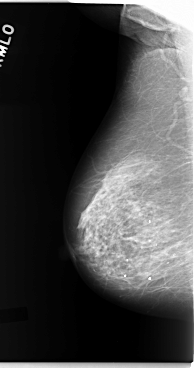

C_0093_1.RIGHT_CC

RIGHT_CC LINES 5872 PIXELS_PER_LINE 3136 BITS_PER_PIXEL 12 RESOLUTION 50 NON_OVERLAY